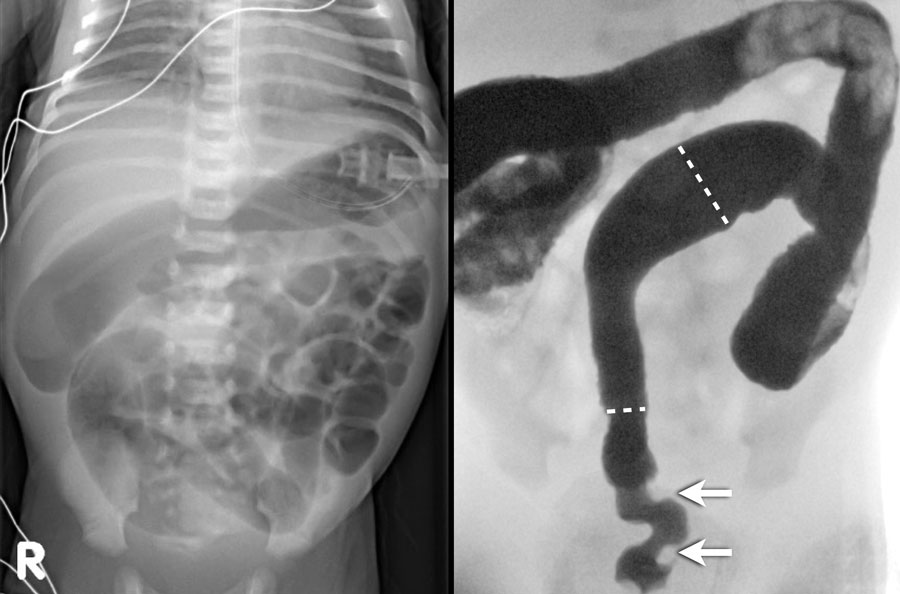

Phim X-quang sẽ cho thấy nhiều quai ruột giãn và không có khí trong đại tràng như hình ảnh bên trái.

Thụt tháo đại tràng sẽ thấy hình ảnh đại tràng nhỏ với thuốc cản quang lấp đầy kết thúc dạng túi cùng ở hồi tràng (mũi tên trên hình bên phải).